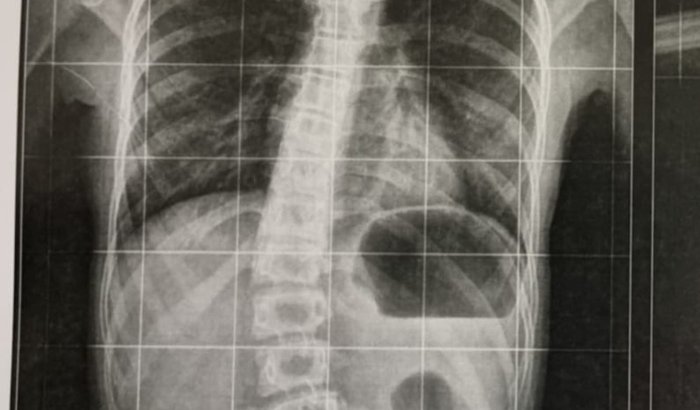

Resumindo: Tenho um cisto crescendo dentro da minha medula espinhal, esse cisto destrói o sistema nervoso e a medula, com o tempo vai me deixar paralisado.

Ou seja, tera sequelas graves (ficar tetraplégico ou paraplégico). A paralisia pode começar nos braços ou nas pernas, dependendo de onde o cisto aumentar primeiro, gerando atrofia dos músculos dos braços e das pernas.

O problema é que aqui no Brasil, a única cirurgia que os médicos fazem para paralisar a evolução dessa doença, é através de uma Cirurgia muito perigosa. Nessa cirurgia os médicos abrem a coluna e colocam um dreno dentro da medula para poder drenar esse cisto. Só que essa técnica é muito arriscada (muito invasiva), ou seja, o paciente corre grandes riscos de ficar paraplégico ou tetraplégicos em alguns casos pode vir a falecer na mesa de cirurgia. Em virtude desse motivo, os médicos só fazem esse procedimento quando o paciente já está paraplégico por conta das sequelas da doença.